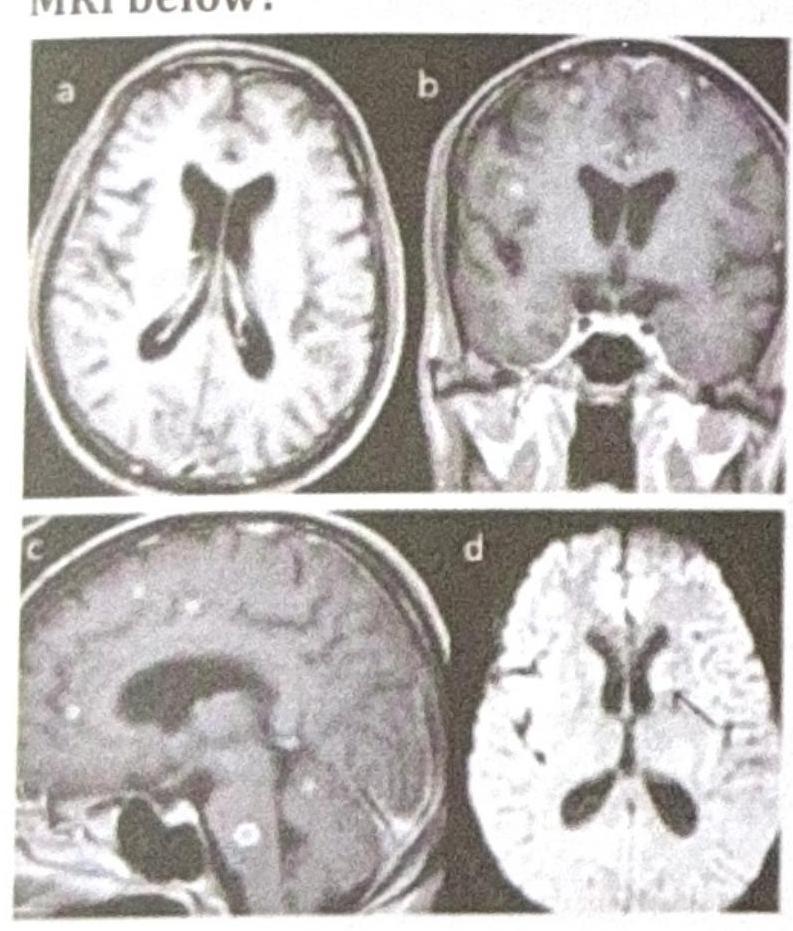

A patient presents with seizures that were controlled with midazolam. Lumbar puncture (LP) revealed no pathology. What is the confirmatory test in the condition shown in the MRI below?

Explanation: ***MR spectroscopy*** - The MRI shows multiple **ring-enhancing lesions**, which, combined with the history of seizures and normal LP, strongly suggests **neurocysticercosis**. - **MR spectroscopy** can detect the specific biochemical markers (e.g., lactate, succinate) within the cyst, which are indicative of the parasitic infection, and can help differentiate it from other lesions like tumors or abscesses. *PET scan* - A **PET scan** primarily assesses metabolic activity and is more commonly used in the evaluation of tumors or neurodegenerative diseases. - It is generally not the primary or confirmatory test for neurocysticercosis, as it does not directly visualize the parasite or its specific biochemical markers. *CBNAAT* - **CBNAAT (Cartridge-Based Nucleic Acid Amplification Test)** is a rapid molecular test primarily used for the diagnosis of **tuberculosis**, not neurocysticercosis. - While tuberculosis can cause CNS lesions, the clinical and imaging presentation (multiple ring-enhancing lesions) is more suggestive of neurocysticercosis, and CBNAAT would not confirm this diagnosis. *MRI serial scan* - **Serial MRI scans** are useful for monitoring the progression or resolution of lesions over time, especially in response to treatment. - However, a serial scan is not a "confirmatory test" for the initial diagnosis; it provides prognostic or follow-up information rather than confirming the etiology.